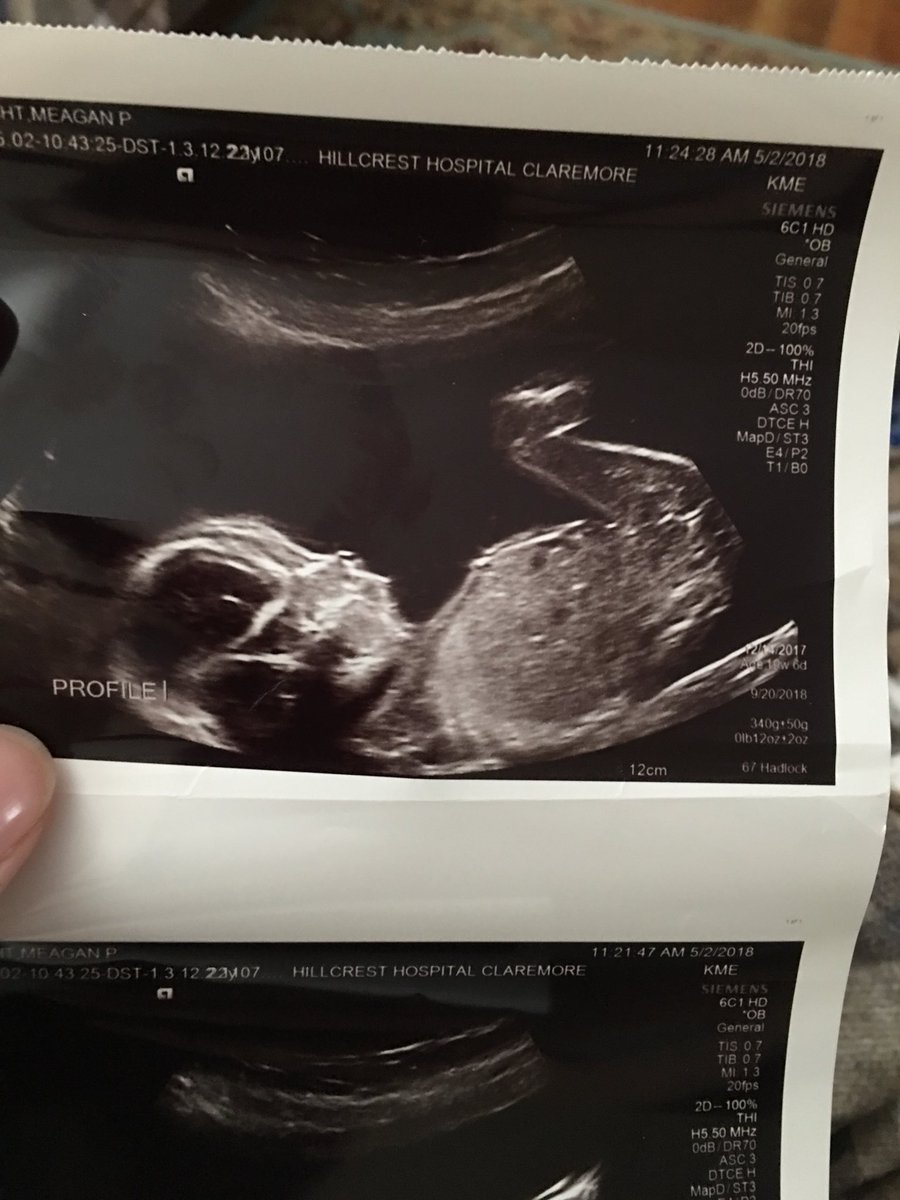

Meagan Wright On Twitter We Had Our 20 Week Anatomy Scan